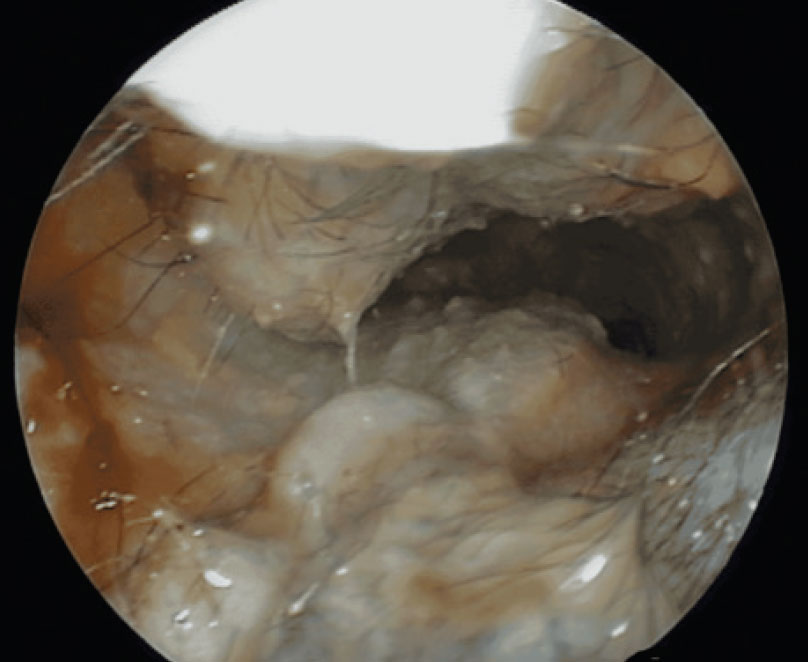

Disruption usually stems from inflammation arising from primary causes, secondary infection, predisposing factors and perpetuating factors. The signs of inflammation: oedema, erythema, increased secretions and hyperplasia, lead to stenosis (see Figure 1), which interferes with the rate of cell turnover, drainage and subsequently the self-cleaning mechanism. Chronic, or recurrent, inflammation results in the progressive thickening of the epidermis and increased secretion and retention of cerumen within the ear canal lumen, all of which favour microbial growth (see Figure 2). This vicious cycle of increased thickening, changes in microbiome, further thickening, etc., leads to fibrosis and calcification of the cartilages making therapy more difficult.

Figure 2: Inflammation, oedema, erythema, hyperplasia, stenosis and purulent exudate can be found in the vertical ear canal.